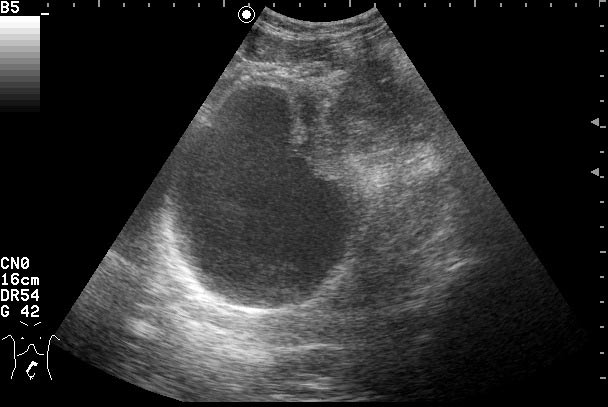

Женщина 42 лет с болями внизу живота, дизурическими явлениями, повышением температуры.

Сонограммы мочевого пузыря

Похоже на опухоль, но по анамнезу я больше склоняюсь к воспалению урахуса!

Согласна с первым постом-возможно нагноение урахуса(и клиника подходит)